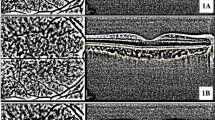

We compared the OCTA metrics in both retina and choroid between DR severity groups. Table 2 shows OCTA quantitative metrics for retinal perfusion, FAZ and CC between groups. CC FD density, regardless of size, increased with DR severity with significant difference between groups, demonstrating higher FD density with increased DR severity (in all CC FD density: 17.06 vs 17.41 vs 17.60 vs 17.62 vs 18.05 vs 18.41, respectively, p trend=0.0004). In superficial FAZ, area and circularity’s trend showed difference between groups, PDR without PRP group has largest superficial FAZ area, longest perimeter and worst circularity perimeter. While severe group has the largest deep FAZ area between groups. In the superficial layer, the FAZ area was larger in the PDR w/o PRP group compared to the severe NPDR group (0.52 vs 0.40 mm2). Conversely, in the deep layer, the FAZ area was larger in the severe NPDR group than in the PDR w/o PRP group (2.28 vs 2.08 mm2). The results of the analysis comparing differences between individual groups are presented in Supplementary Table 1. Representative images of the OCTA data extraction process are shown in Fig. 1.

Trends of OCTA metrics in each group were showed in Fig. 2. CC FV increased with DR severity (Fig. 2A). The FAZ area in the deep layer was the largest in the severe NPDR group and whereas in the superficial layer it was largest in those with PDR. (Fig. 2B). The trend in the superficial layer showed that large vessels dilated and increased at the onset of the DR stage (Fig. 2C). PD and VD in deep layer showed similar change along the severity (Fig. 2D).